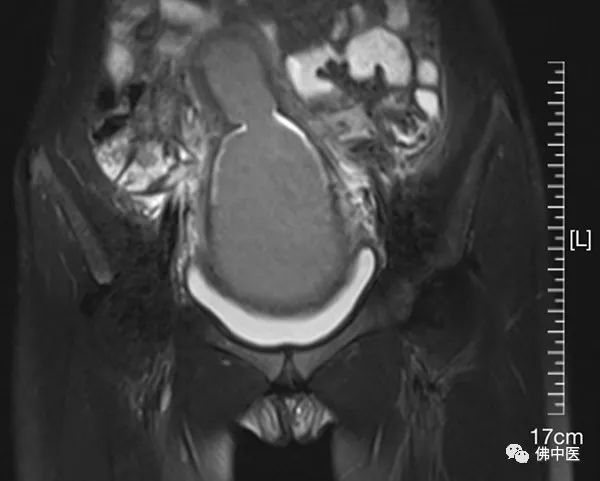

我院MRI检查显示为先天性阴道闭锁

我院MRI检查显示积血形成肿块

术前MRI提示,患儿双侧附件区卵巢形态及信号未见异常,子宫及阴道体积增大,子宫腔及阴道内积血,结合病史,符合先天性阴道闭锁。由于女性生殖器官发育异常多合并宫颈闭锁、泌尿系统发育异常,手术部位解剖结构术前难以完全明确,从而为手术增加了不少难度。因此,术前游哲辉与罗健主治中医师、韦燕医生等在科内做了详细的讨论交流,并制定手术方案和设计术后模具。